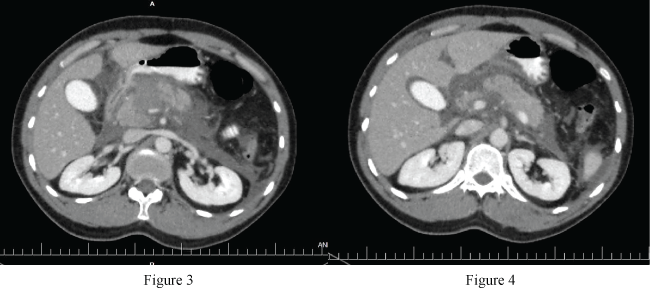

Oral intake of the patient was closed, and he was continued to be followed with IV hydration at the 12 hour of patient's follow up, body temperature was increased to 38.2, leucocytosis and hyperamilasemia were occur. (wbc: 14.200/ul, hb: 11.9 g/dl amylase: 578 u/l), therefore control IV contrast-enhanced abdominal CT has been performed to the patient. In left lobe of liver, a view compatible with grade 2 laceration was observed, and hypodense area in the neck of the pancreas was observed compared to surrounding pancreatic tissue. It was interpreted aspancreaticlaceration. Then, informed consent was obtained from the patient, and explorative laparotomy was planned with "acute abdomen" and "pancreatic laceration"? preliminary diagnosis (Figure 3 and Figure 4).

Figure 3-4: Hypodense area in the neck of the pancreas was observed compared to surrounding pancreatic tissue.